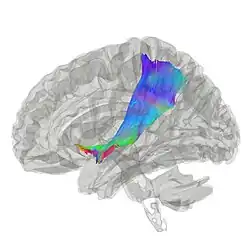

La capsule extrême (en latin : capsula extrema) est un ensemble de tractus de fibres blanches (formées d'axones) situées entre le claustrum (appelé également l'avant-mur) et le cortex insulaire[1]. Cette capsule extrême est aussi décrite comme une fine capsule de substance blanche en tant que fibres d'association (en) corticocorticales (c'est-à-dire que ces fibres sont responsables de relier le cortex cérébral avec une autre aire corticale)[2]. La capsule extrême est séparée de la capsule externe par le claustrum, et la capsule extrême sépare le claustrum du cortex insulaire, et tous ces éléments se trouvent latéraux par rapport aux composants du corps strié[2],[3].

Allant de la ligne médiane du cerveau vers le côté, la capsule extrême est la plus externe par rapport à la capsule externe et à la capsule interne[4].

Elle est plus facilement visible dans une coupe horizontale (transversale), juste latéralement au claustrum.